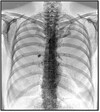

Q

What pathology is seen here? How do we know?

A